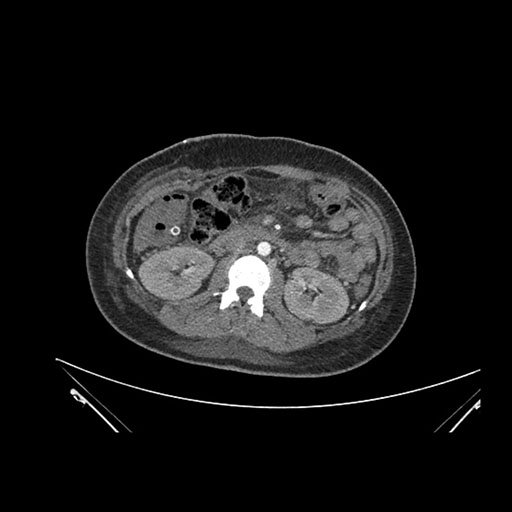

Imaging Analysis

Look through the patient's CT scan to identify any areas of concern for the necessary procedure.

Axial Arterial

Based on initial findings, which issue(s) would you be most concerned about?